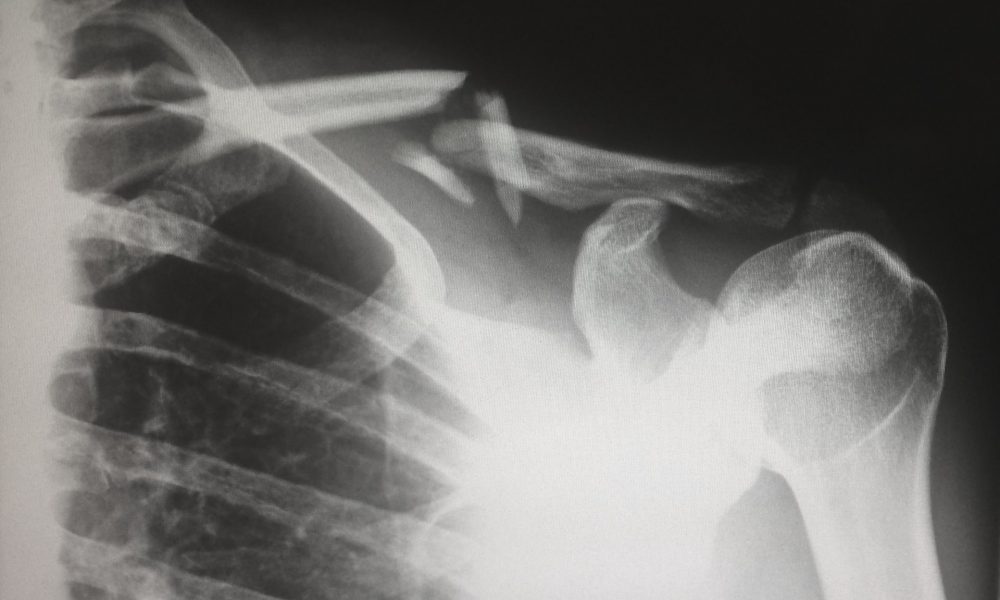

Falls are the most fatal accident to strike adults over 55. They are also the most common cause of accidents that result in broken bones and...